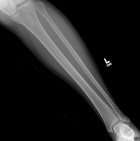

50 year old female with painful mass in left leg for one month

Zoom image: Radiological image Radiological image.